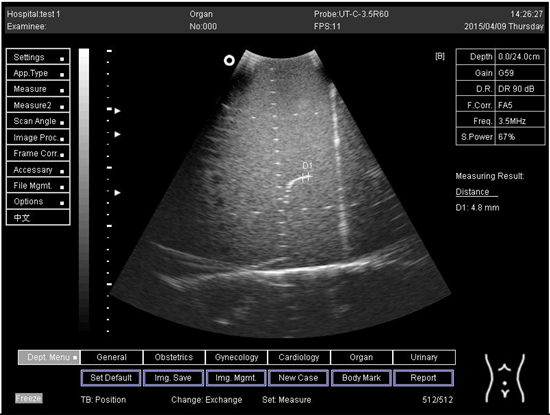

24.0Axial resolution

Biomimetics 07 00130 i021

D1 = 4.8

D2 = 4.1

24.0Lateral resolution

Biomimetics 07 00130 i022

D1 = 5.3